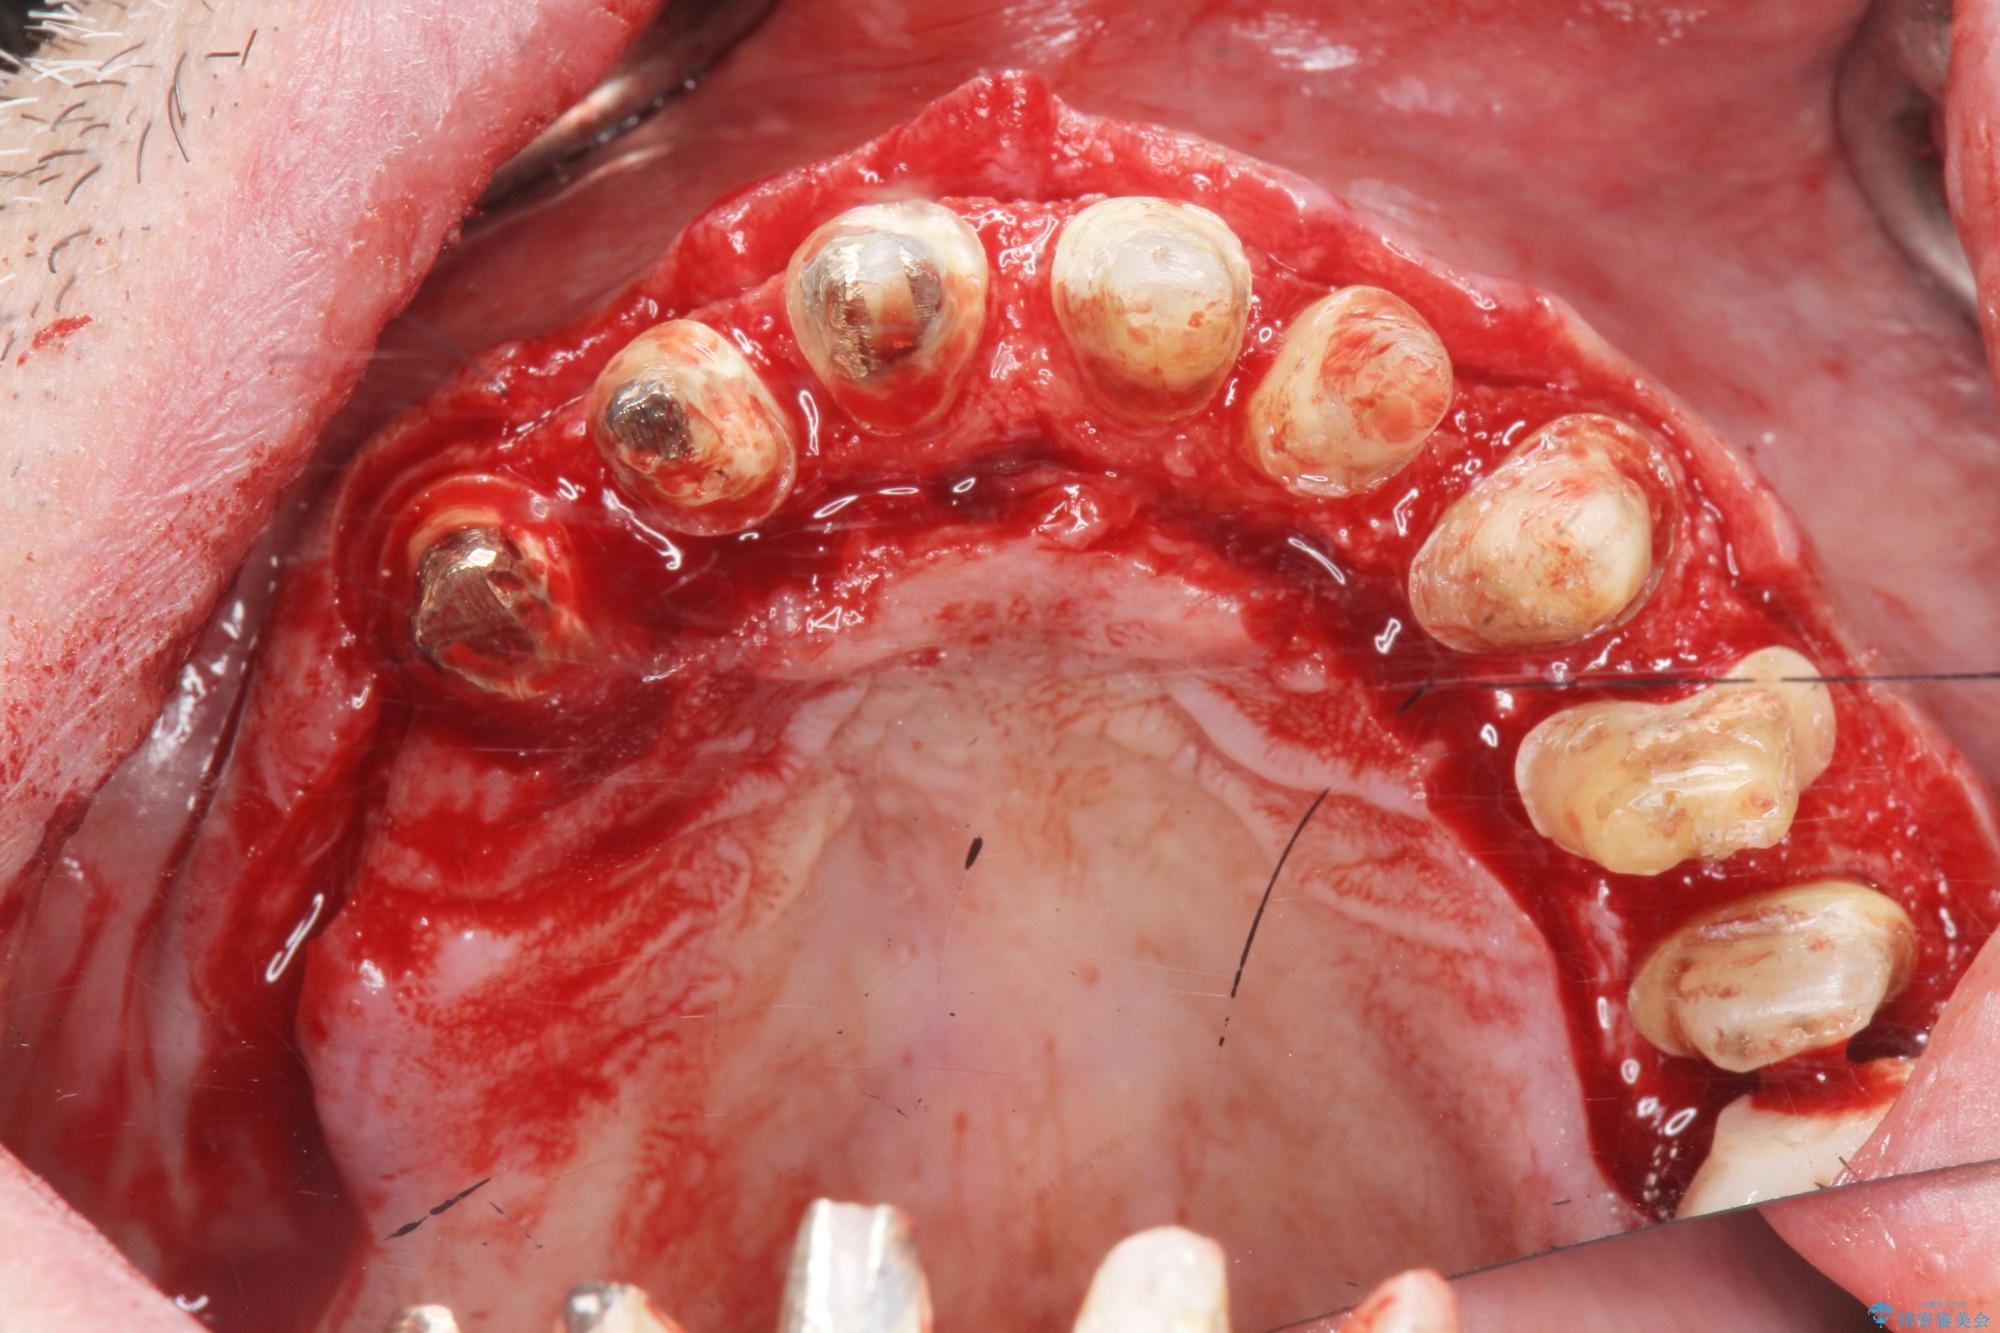

- 「セラミック治療を他院で受けたが、それ以来歯ぐきが腫れ違和感がある、改善してほしい。」と歯ぐきの状態改善を希望され来院されました。

歯周組織検査を行うと歯ぐきからは容易に出血し、X線検査より歯とセラミッククラウンの適合が悪い(ピッタリと合っていない)状態が示唆され、歯ぐきの炎症を惹起している状態でした。

セラミッククラウンを除去し仮歯を装着し、歯周外科手術を行い歯ぐきの状態を改善したのち、適合の良いセラミッククラウンを再作製をする治療計画としました。